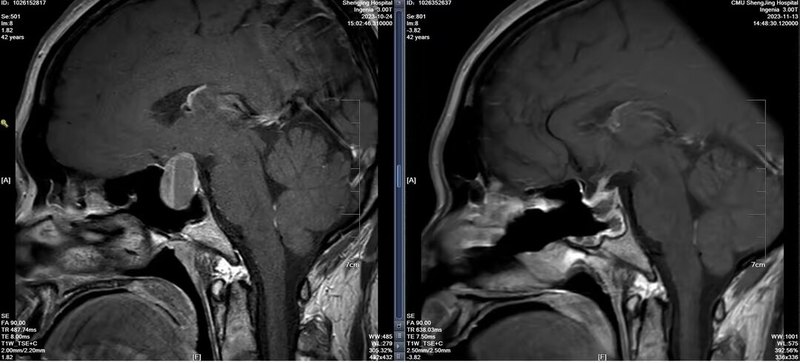

垂體瘤為什么會復發(fā)

垂體瘤為什么會復發(fā),今天跟大家聊一聊這個話題。最近遇到一位年輕的垂體瘤復發(fā)的患者,第一次發(fā)現是在2021年,術前有停經泌乳的表現,垂體激素化驗顯示泌乳素升高,做垂體增強磁共振發(fā)現腫物,診斷為泌乳素腺瘤??诜幬镏委煱肽晖=浢谌闆]有改善,隨后又出現視力模糊的癥狀,復查垂體增強磁共振發(fā)現腫物增大,壓迫視神經。這時候做了第一次經鼻內鏡垂體瘤的手術,術后效果很明顯,停經泌乳癥狀消失,視力也得到改善。一年以后2022年時復查垂體增強磁共振顯示垂體大小正常,抽血化驗垂體激素也未見異常。2023年7月開始出現陣發(fā)性頭痛,隨后再次出現視力模糊,但這次沒有出現停經泌乳改變。復查垂體增強磁共振提示有垂體瘤復發(fā)跡象,但是腫物大小還未對視神經造成明顯壓迫。垂體激素化驗正常。10月份再次復查顯示垂體瘤繼續(xù)生長,伴局部卒中出血,明顯壓迫視神經,隨后做了第二次經鼻內鏡手術,術后恢復良好(見下圖),順利出院。那么究竟是什么原因導致垂體瘤復發(fā)呢?目前還沒有明確的致病機制,但總的來說,應從以下幾個方面來分析:1.對于有功能的垂體瘤,通俗來講就是垂體分泌的激素中一種或幾種激素出現異常,這種異常會反饋性的造成垂體瘤細胞異常增生,從而導致垂體瘤復發(fā)。在這種情況下,無論第一次手術切除率是否滿意,都應監(jiān)測垂體激素的變化,這種垂體瘤復發(fā)時一般生長較快。2.對于無功能性垂體瘤,第一次手術全切后一般很少復發(fā),即使復發(fā)腫瘤生長也很慢。但如果第一次手術未實現全切,術后應注意影像學隨訪監(jiān)測腫瘤是否復發(fā)。在這例患者中,雖然第一次為有功能性垂體瘤,但是在第二次復發(fā)過程中未發(fā)現垂體激素異常,腫瘤體積變大的主要原因還是因為垂體瘤卒中所致。如果發(fā)現垂體瘤復發(fā),我們應該采取什么樣的診療策略呢?1.對于小的,無功能性的垂體瘤,以觀察為主,可以定期復查垂體激素以及垂體增強磁共振。這種垂體瘤一般生長緩慢,可以長期隨訪。2.對于小的,有功能性的垂體瘤,比如泌乳素腺瘤或者生長激素腺瘤,可以應用相對應的藥物,溴隱亭或生長抑素等來控制腫瘤的生長。3.對于腫瘤較大,已經壓迫周圍神經的,可采取二次手術。絕大多數復發(fā)垂體瘤手術方案首選經鼻內鏡手術,部分病例需采取開顱手術或者聯合手術。復發(fā)垂體瘤治療有哪些注意事項?由于是二次手術,解剖結構不清晰會造成手術困難,造成出血和神經副損傷風險的增加。其次,由于鞍底結構已經破壞,二次手術以后腦脊液漏的風險也會增加。最后,二次手術的全切率較第一次也會降低。建議垂體瘤患者朋友們不要忽視定期復查的重要作用,及早發(fā)現腫瘤復發(fā),為下一步治療爭取寶貴的時間。也祝大家早日康復!